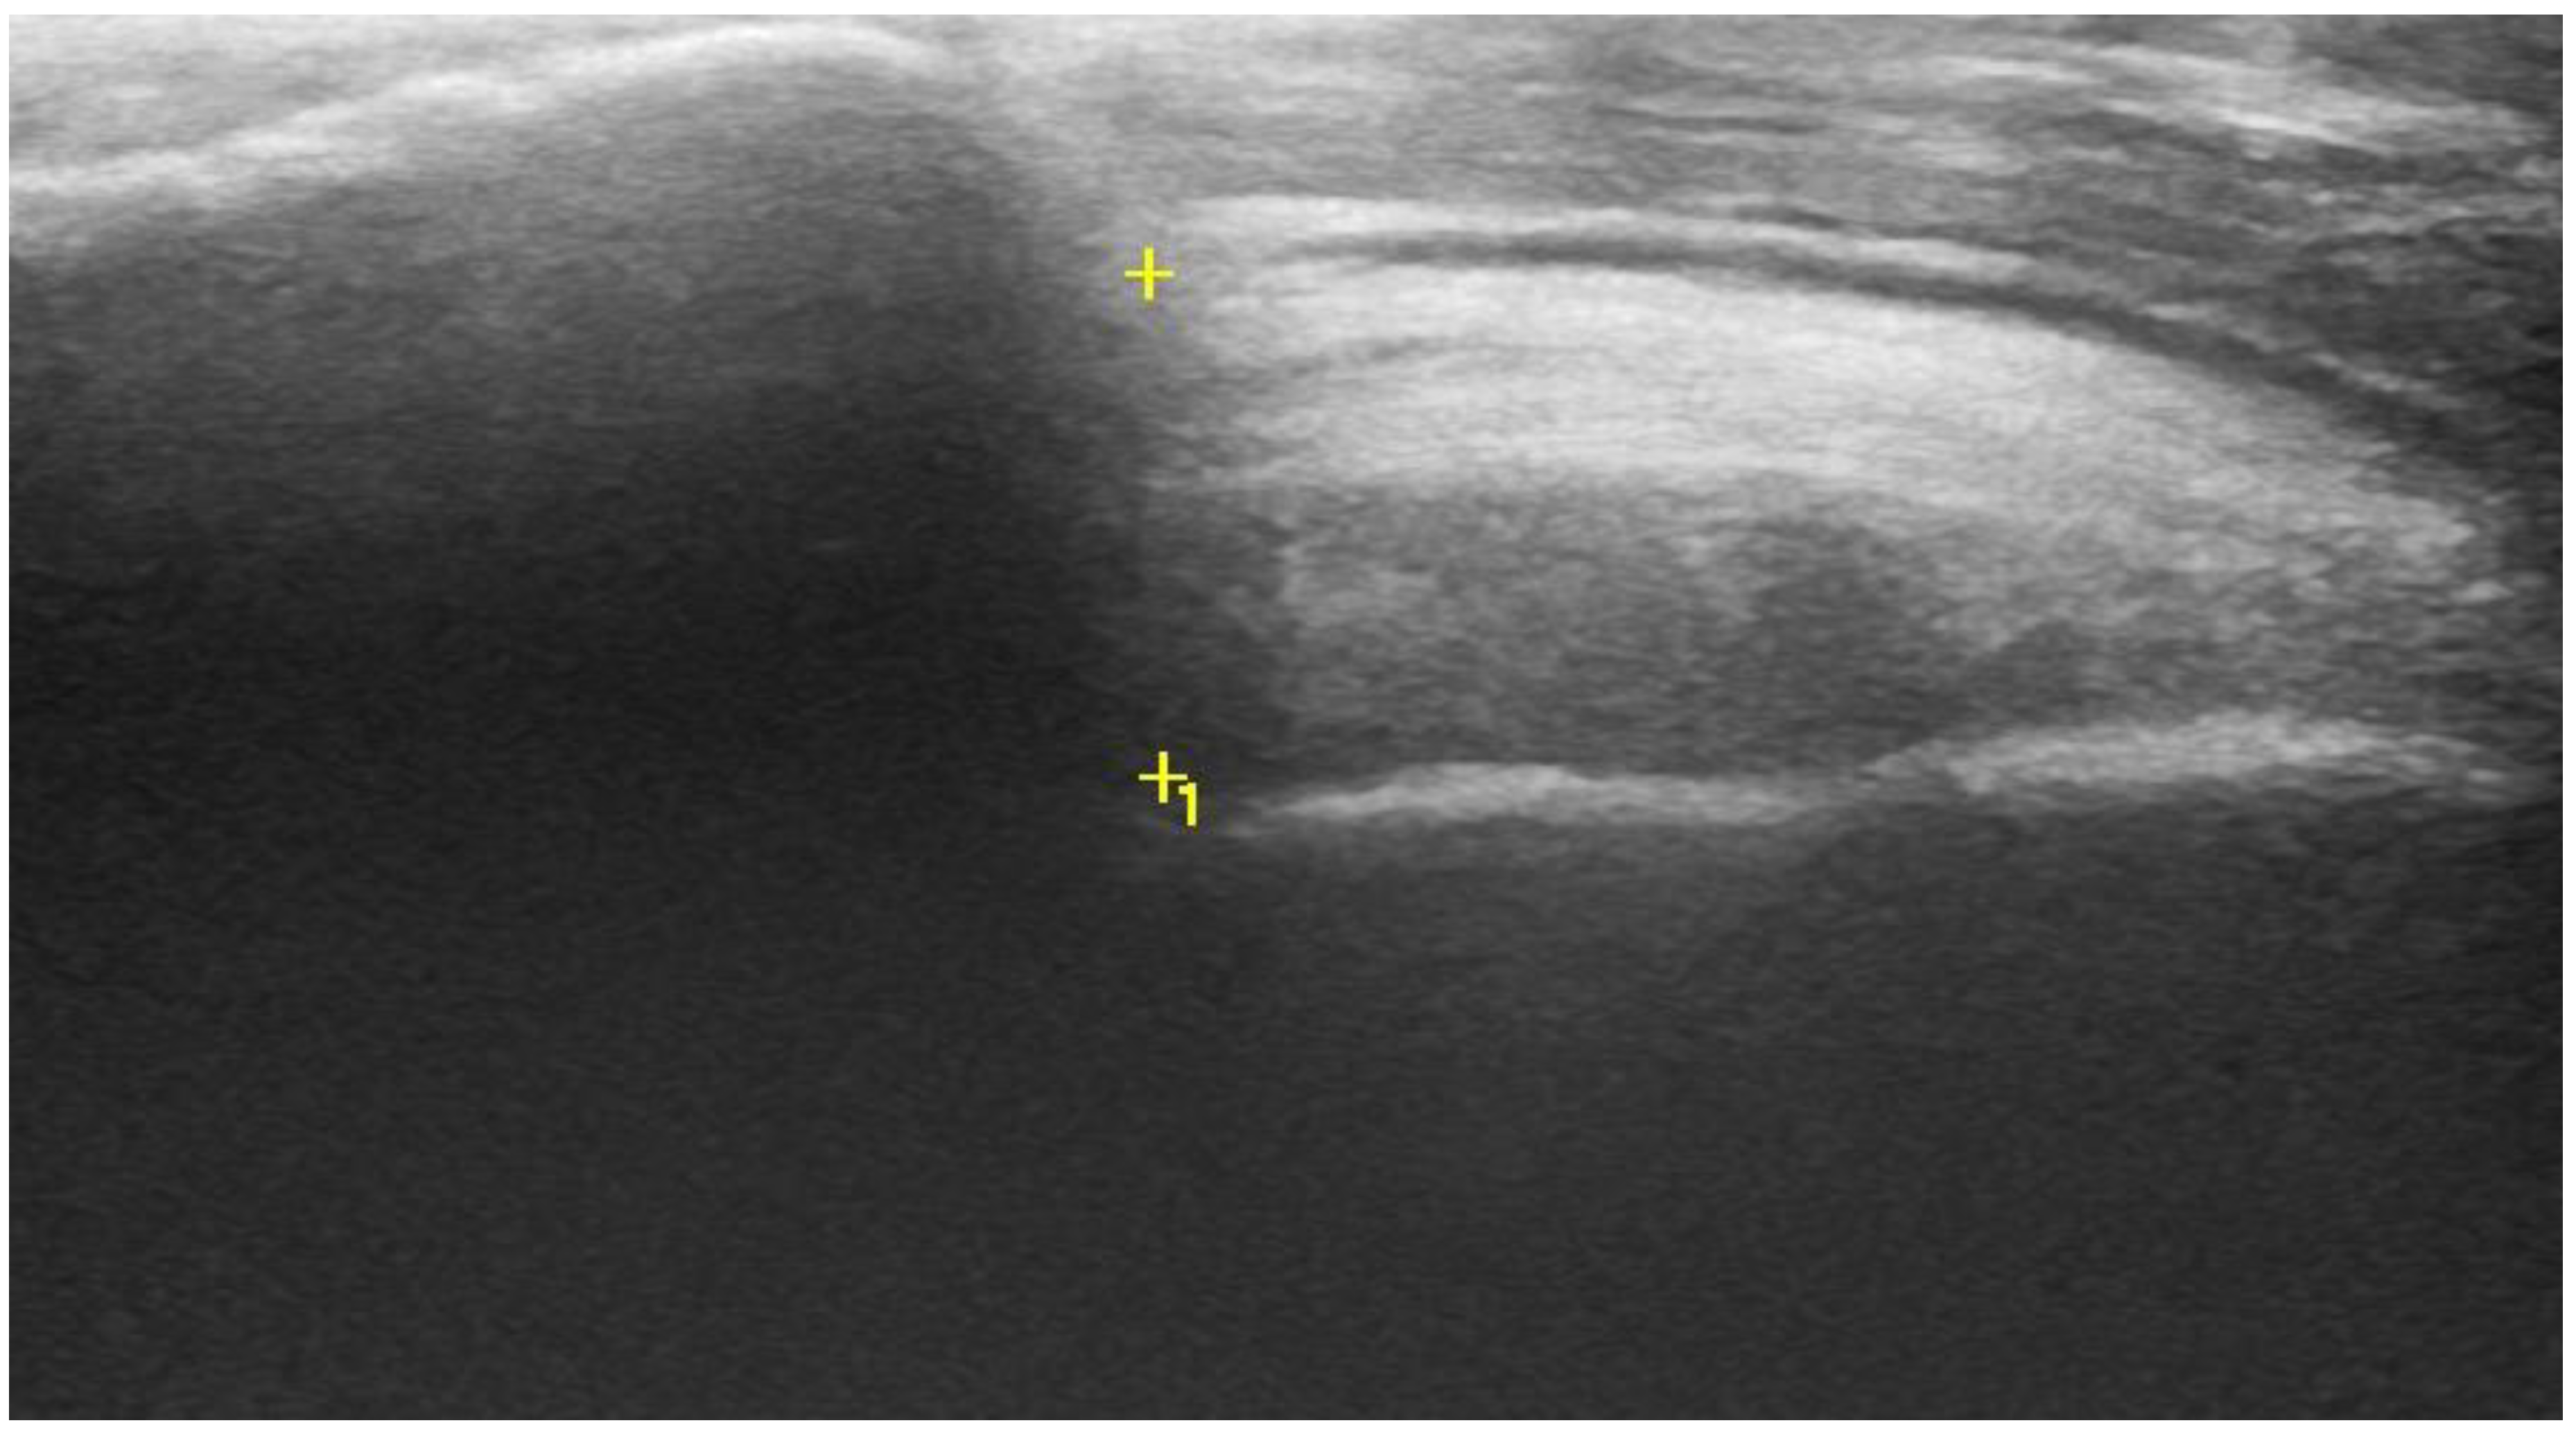

2.2. Acromiohumeral Distance (AHD)